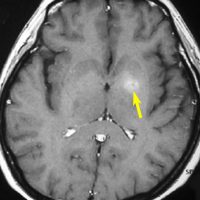

1990年代に放射線治療をした古い例です。定位生検術の後で全部の脳に40グレイという線量を照射しました。左から2番目の写真で腫瘍は消えています。でも,6ヶ月後の3番目の写真では脳がやせてきています(脳萎縮)。患者さんの精神機能は著しく低下しました(いわゆる認知障害)。4番目の写真は治療後8ヶ月目のものですが,すでに左側に小さな再発が見られます。全部の脳にあてる放射線の量はできる限り少ない方がいいのです。2017年時点では30グレイというのが標準的線量です。